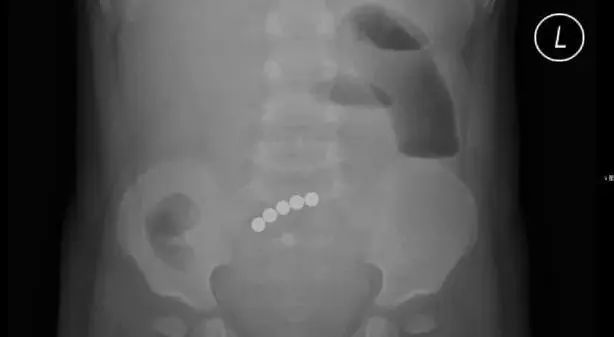

心急如焚的爸妈把孩子带到深圳市儿童医院,做了个腹部X光检查,结果发现,小安的肠道内居然有5颗连在一起的圆珠子!

▽

小安身体里,磁珠吸附处的肠壁已经出现了3处坏死穿孔,大量粪液已经流进肚子里了。